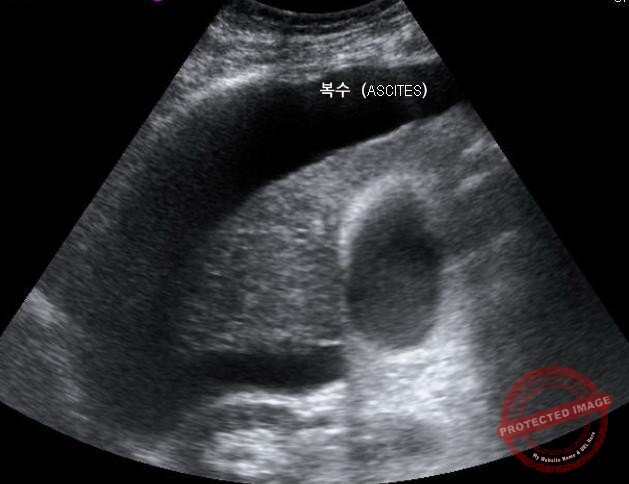

복수가 찬 간경변 환자의 간 초음파 이미지 (출처 : 위키미디어)

문진(바이러스 간염, 음주 여부, 간 손상을 유발하는 물질 사용 등)과 신체 진찰(복수, 다리 부종 등)은 기본이며 혈액검사, 복부초음파검사, 복부 전산화단층촬영(CT) 등의 영상 검사를 합니다. 또한 상부 위장관 내시경 검사도 합니다.

혈액검사로 간 기능과 간암 혈액 표지자(알파태아단백, α-fetoprotein)를 확인합니다. 복부 초음파와 전산화단층촬영(CT)으로 간 모양 변화, 복수 여부, 비장비대 등의 이상 소견을 확인하며 특히 간암 동반 여부를 꼭 확인합니다. 상부 위장관 내시경을 통해 식도정맥류의 동반 여부도 확인합니다.